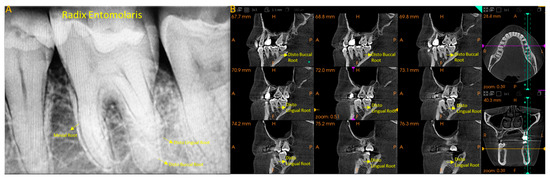

Radix Entomolaris and Complex Incisor Anatomy in a Saudi Cohort: A Retrospective Study